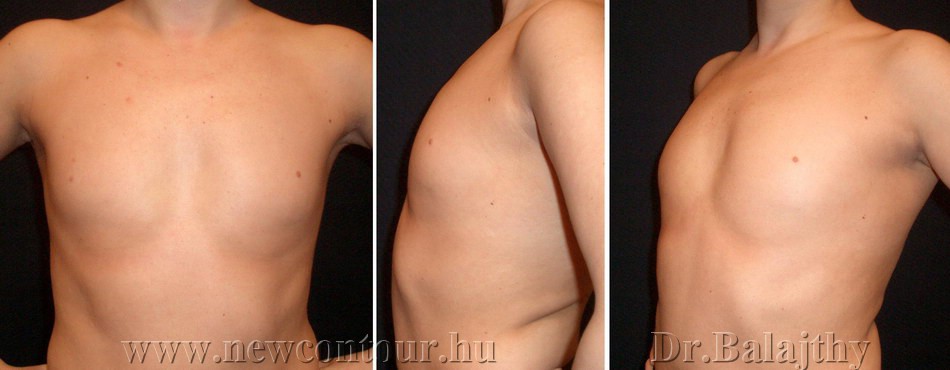

Синдром Поланда представляет собой сочетание деформации грудной клетки и отсутствия или гипоплазии грудных мышц и молочной железы, связанное с укорочением и брахисиндактилией верхней конечности. Клиническая картина широко варьируется; следовательно, реконструктивные процедуры должны быть адаптированы к деформации, начиная от стабилизации или увеличения грудной стенки, динамического переноса мышц, изменения положения соска и ареолы и увеличения груди с использованием протеза или переноса аутологичной ткани. Другие врожденные аномалии молочной железы включают избыточные соски и ареолы (полителия) и груди (полимастия), которые обычно можно обнаружить на эмбриональном грудном гребне. Отсутствие соска, ареолы (ателии) или ткани молочной железы (амастия) встречается реже.

Синдром Поланда назван в честь Альфреда Поланда, описавшего это состояние в 1841 году.Два предыдущих описания отсутствия грудной мышцы были зарегистрированы в 1826 и 1839 годах без связанной с этим деформации кисти. Синдром Поланда представляет собой сочетание аномалий грудной клетки и верхних конечностей, обычно односторонних, хотя сообщалось о нескольких двусторонних случаях. Чаще встречается у мужчин и справа. Распространенность, приблизительно 1 на 20 000–30 000 рождений, 1 считается недооцененной. Причина синдрома до сих пор остается спорной, но многие авторы поддерживают гипотезу об аномальном развитии сосудистой сети плода в области, вызывающей наблюдаемые дефекты. 2 Другие синдромы (Мебиуса, Клиппеля-Фейля, деформации Шпренгеля) могут быть связаны. Большинство случаев носят спорадический характер, хотя есть сообщения о генетической передаче.

Синдром включает деформацию или отсутствие ребер, частичное или полное отсутствие грудных мышц, особенно грудино-реберной головки большой грудной мышцы, что приводит к отсутствию передней подмышечной складки. Иногда можно обнаружить перепонку подмышечной впадины с аномальной фиброзной полосой от грудной клетки до плечевой кости.В большинстве случаев отмечается гипоплазия или отсутствие молочной железы, ареолы и подкожной клетчатки. Верхняя конечность часто укорочена при брахисиндактилии кисти. 3 На ипсилатеральной стороне могут поражаться и другие мышцы, в том числе передняя зубчатая мышца и широчайшая мышца спины. 4 Реконструктивные варианты многочисленны в зависимости от представления и потребностей пациента (). Необходимо провести тщательный анализ дефекта: отсутствие или деформация ребер, полное или частичное отсутствие грудной мышцы (), наличие передней подмышечной складки, перепонки подмышечной впадины (), размер и расположение сосково-ареолярного комплекса. (NAC) и ткань молочной железы.Плечо и лопатка могут иметь значительную степень асимметрии (возвышение), а гемиторакс на пораженной стороне часто уже. Следует тщательно исследовать ипсилатеральную широчайшую мышцу спины, поскольку она также может отсутствовать. В этом случае при планировании хирургического вмешательства необходимо учитывать свободную трансплантацию мышц. Аномалии сосудистой анатомии могут осложнить трансплантацию свободной ткани.

( A ) Синдром Поланда с полным отсутствием грудной мышцы и ткани молочной железы.Обратите внимание на расположенный сверху и гипоплазированный сосок и ареолу (перепечатано с разрешения Caouette-Laberge L, Bortoluzzi P. Коррекция асимметрии груди у подростков. В: Hall Findley E, Evans GRD, eds. Эстетическая и реконструктивная хирургия груди. Филадельфия, Пенсильвания. : Saunders Elsevier; 2010: 601–629). ( B ) Синдром Поланда с подмышечной перемычкой, отсутствием грудино-реберной грудной мышцы и гипоплазией молочной железы. (Перепечатано с разрешения Caouette-Laberge L, Bortoluzzi P. Коррекция асимметрии груди у подростков.В: Холл Финдли Э., Эванс GRD, ред. Эстетическая и реконструктивная хирургия груди. Филадельфия, Пенсильвания: Saunders Elsevier; 2010: 601-629.)

( A ) Синдром Поланда с минимальной мускулатурой в подключичной области, отсутствием передней подмышечной складки и гипоплазией молочной железы в адекватном месте (Перепечатано с разрешения Caouette-Laberge L, Bortoluzzi P. Коррекция асимметрии груди у подростков. В: Hall Findley E, Evans GRD, редакторы Эстетическая и реконструктивная хирургия груди.Филадельфия, Пенсильвания: Saunders Elsevier; 2010: 601–629). ( B ) Через два года после пересадки мышц и увеличения груди с помощью подмышечного грудного имплантата, вставленного во время пересадки мышц, обратите внимание на шрам на проксимальной части руки для повторного прикрепления сухожилия к плечевой кости. ( C ) Минимальная деформация спины после переноса широчайшей мышцы (круглый пронатор остается для задней подмышечной складки) (Перепечатано с разрешения Caouette-Laberge L, Bortoluzzi P. Коррекция асимметрии груди у подростков.В: Холл Финдли Э., Эванс GRD, ред. Эстетическая и реконструктивная хирургия груди. Филадельфия, Пенсильвания: Saunders Elsevier; 2010: 601–629). ( D ) Срединно-грудной рубец через 2 месяца после переноса широчайшей мышцы (перепечатано с разрешения Caouette-Laberge L, Bortoluzzi P. Коррекция асимметрии груди у подростков. В: Hall Findley E, Evans GRD, eds. Эстетическая и реконструктивная хирургия груди , Филадельфия, Пенсильвания: Saunders Elsevier, 2010: 601–629).